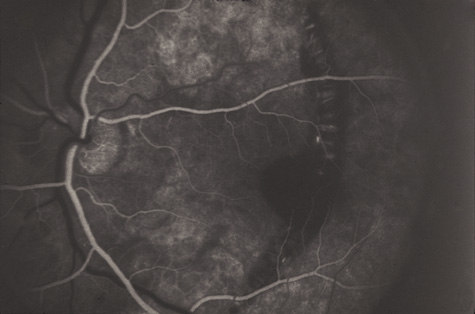

CHOROIDAL INJURIES

Posterior choroidal ruptures are probably caused by anterior-posterior compression and equatorial expansion. The retina is relatively elastic, and the sclera is relatively tough. Both resist ruptures. Bruch's membrane, on the other hand, is inelastic and more prone to rupture. The overlying RPE and underlying choriocapillaris are also torn, but in most cases, the deep choroidal blood vessels remain intact (Fig. 19). Rupture of the choriocapillaris often results in subretinal hemorrhage. Patients with angioid streaks and other conditions known to be associated with a inelastic and fragile Bruch's membrane are especially vulnerable to choroidal rupture (Fig. 20).

Initially, a choroidal rupture may be obscured by a subretinal hemorrhage caused by tearing of the choriocapillaris. Later, after the blood has resorbed, a white curvilinear streak concentric to the optic disc is seen. Only rarely is a rupture oriented radially with respect to the optic disk. Most are temporal to the disc and single, although nasal and multiple ruptures can also occur (Fig. 21).

Fig. 21. A: Choroidal rupture concentric to the optic disc. B: Multiple choroidal ruptures. The visual acuity is 20/20.

If the choroidal rupture is under the foveola or if an associated subretinal hemorrhage extends under the foveola, the visual prognosis is generally poor (Fig. 22); however, a recent study showed that even patients with foveal or multiple choroidal ruptures can regain good central vision after extended follow-up.86 If the rupture is elsewhere the prognosis is good because the overlying nerve fiber layer is almost never torn. Therefore, a rupture can be located between the disc and the macula and yet not affect the visual acuity (Fig. 21).